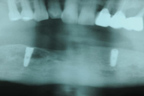

施行鼻竇升高術及骨粉充填。

X光片可見兩植體在鼻竇下緣。